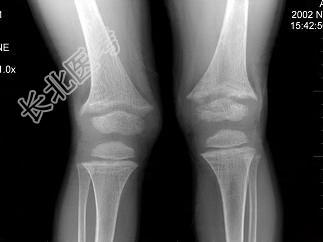

- 单项选择题男,6岁, 睡眠差,夜惊, 多汗;出牙较迟; 血清磷减低、血清钙减低、碱性磷酸酶升高,请结合图像选择最佳选项  (    )

A、维生素D缺乏病

B、骨软化症

C、先天性骨梅毒

D、肾性维生素D缺乏病

E、脆骨病